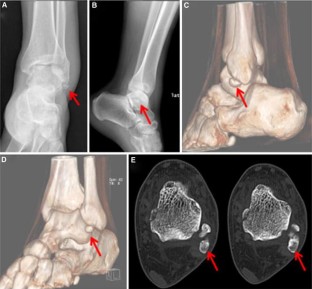

Fig. 1